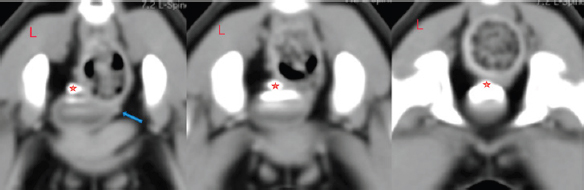

The CT scan was performed on a GE BrightSpeed 8 CT machine. The patient was positioned with the head pointing to the gantry in dorsal recumbency. Anesthesia was maintained with isoflurane gas flowing through a fourth-size endotracheal tube. A helical scan acquisition was performed through points of I (eight thoracic vertebra) through S (the caudal portion of os pubis) with slice gaps of 1.25 mm. A total of 448 images were taken twice—pre and post-contrast medium infusion (iohexol, Omnipaque ® 647 mg/ml–2.4 ml i.v.). Analyzing soft tissue reconstructions in transverse, sagittal, and dorsal planes of the CT tomograms, we found that the left ureter opening is pathological (Fig. 1).

An orifice is found immediately where the urethra is formed; therefore, urine flows outward bypassing the urinary bladder and sphincter. Ectopy type is thought to be intramural due to visible thin mucous membrane partition between the bladder and ureter. It extends from the urethra to the anatomical ureter opening location. As seen in other ectopy cases, we observed a complex of pathologies: the urinary bladder was localized more caudally, and the urinary tract was shorter than usual (Fig. 2). Cystoscopy was performed with the instrument shown in Figure 3.

Fig. 2. Post-contrast transverse reconstructed CT study images. Red stars indicate the left ureter opening into the urinary bladder. The blue arrow shows the contralateral ureter position. They both cross the wall of the bladder in a normal position, but the left one is excreting urine through a channel into the urethra. An orifice is found immediately where the urethra is formed; therefore, urine flows outward bypassing the urinary bladder and sphincter.